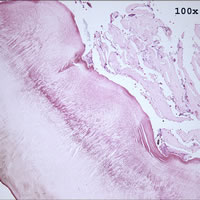

Case

98:

A 5-year-old girl developed an earache after vacationing in Belize with

her parents. A few months after returning from the vacation, her

parents took her to a New York City hospital for the earache where a biopsy

specimen was taken from her left ear. Her parents reported that

she had gone swimming during the trip. The following images

are from H & E (hematoxylin and eosin) stained sections of the biopsy. What

is your diagnosis? Based on what criteria?